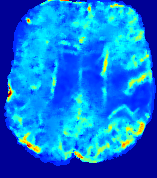

LesionRefer to captionRefer to captionRefer to captionRefer to captionRefer to captionRefer to caption𝐕rgbsubscript𝐕𝑟𝑔𝑏{\bf{V}}_{rgb}Refer to captionRefer to captionRefer to captionRefer to captionRefer to captionRefer to caption𝐕2subscriptnorm𝐕2{\|\bf{V}}\|_{2}Refer to captionRefer to captionRefer to captionRefer to captionRefer to captionRefer to captionRefer to caption3.53.53.52.82.82.82.12.12.11.41.41.40.70.70.70.00.00.0(mm/s)𝑚𝑚𝑠(mm/s)D𝐷DRefer to captionRefer to captionRefer to captionRefer to captionRefer to captionRefer to captionRefer to caption0.0200.0200.0200.0160.0160.0160.0120.0120.0120.0080.0080.0080.0040.0040.0040.0000.0000.000(mm2/s)𝑚superscript𝑚2𝑠(mm^{2}/s)Slice #1Slice #2Slice #3Slice #4Slice #5Slice #6

Figure 4: PIANO feature maps for another patient in the ISLES 2017 training set, where the lesion is located in the right hemisphere. Top row: segmented stroke lesion region (white) on different slices. The corresponding slices for the PIANO feature maps are shown in the following rows.

For a better insight into an estimated velocity field 𝐕𝐕{\bf{V}} and diffusion field 𝐃𝐃{\bf{D}}, we compute the following maps: (1) 𝐕rgbsubscript𝐕𝑟𝑔𝑏{\bf{V}}_{rgb}: Color-coded orientation map of 𝐕=(Vx,Vy,Vz)T𝐕superscriptsuperscript𝑉𝑥superscript𝑉𝑦superscript𝑉𝑧𝑇{\bf{V}}=(V^{x},V^{y},V^{z})^{T}, obtained by normalizing 𝐕𝐕{\bf{V}} to unit length and mapping its 3 components to red, green, blue respectively; (2) 𝐕2subscriptnorm𝐕2\|{\bf{V}}\|_{2}: 222 norm of 𝐕𝐕{\bf{V}}; (3) D𝐷D: scalar field in Eq. 5.

Fig. 3 and Fig. 4 show the PIANO feature maps estimated from two ISLES 2017 patients: all are highly consistent with the lesion in both cases. Details of the blood flow trajectories are revealed in 𝐕rgbsubscript𝐕𝑟𝑔𝑏{\bf{V}}_{rgb} by the ridged patterns and the sharp changes of colors in the unaffected (right) hemisphere, while the flat patterns appearing within the lesion provide little directional information about the velocity and indicate low velocity magnitudes. Velocity magnitudes are more directly visualized via 𝐕2subscriptnorm𝐕2\|{\bf{V}}\|_{2}, from which one can easily locate the lesion where 𝐕2subscriptnorm𝐕2\|{\bf{V}}\|_{2} is low. D𝐷D also indicates lower diffusion values in the lesion, though with less contrast potentially due to the fact that it captures the accumulated effect of CA diffusion at the voxel-level.